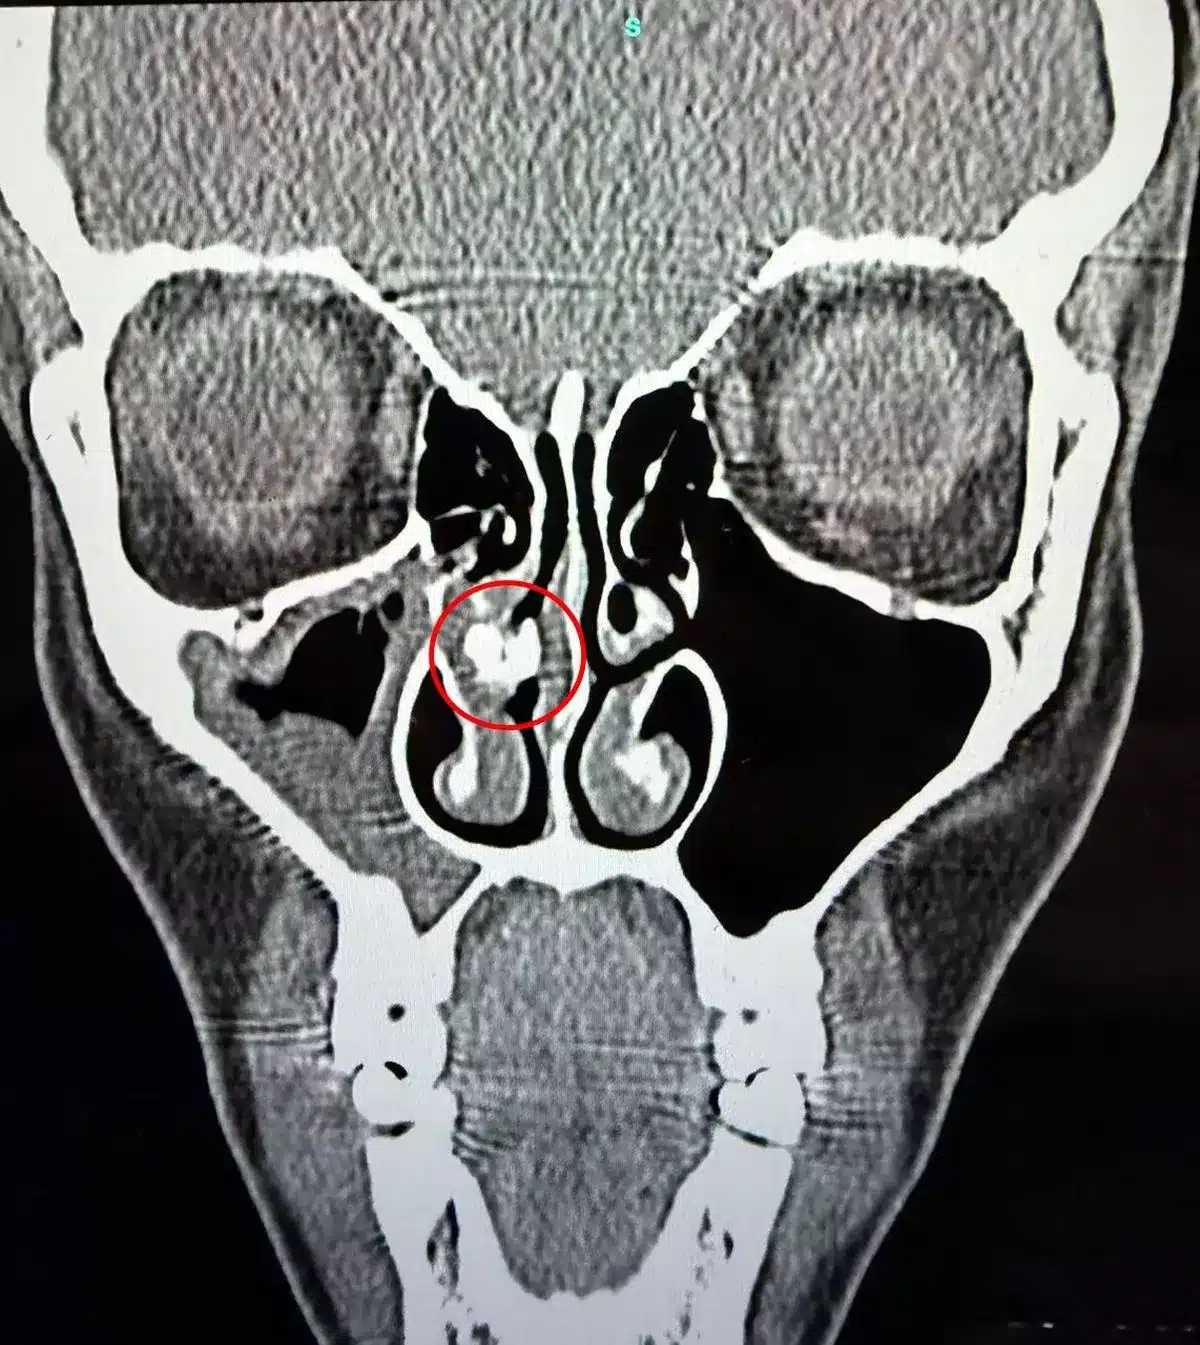

แพทย์จึงทำการตรวจอย่างละเอียด พร้อมส่งตรวจด้วยเครื่องซีทีสแกน ก่อนพบจุดผิดปกติคล้ายหินปูนหรือสิ่งอุดตันในโพรงจมูก จากนั้นจึงใช้กล้องส่องและเครื่องมือพิเศษคีบสิ่งดังกล่าวออกมา ใช้เวลานานเกือบ 1 ชั่วโมง ท่ามกลางความลุ้นระทึกว่าสิ่งที่พบคืออะไรกันแน่